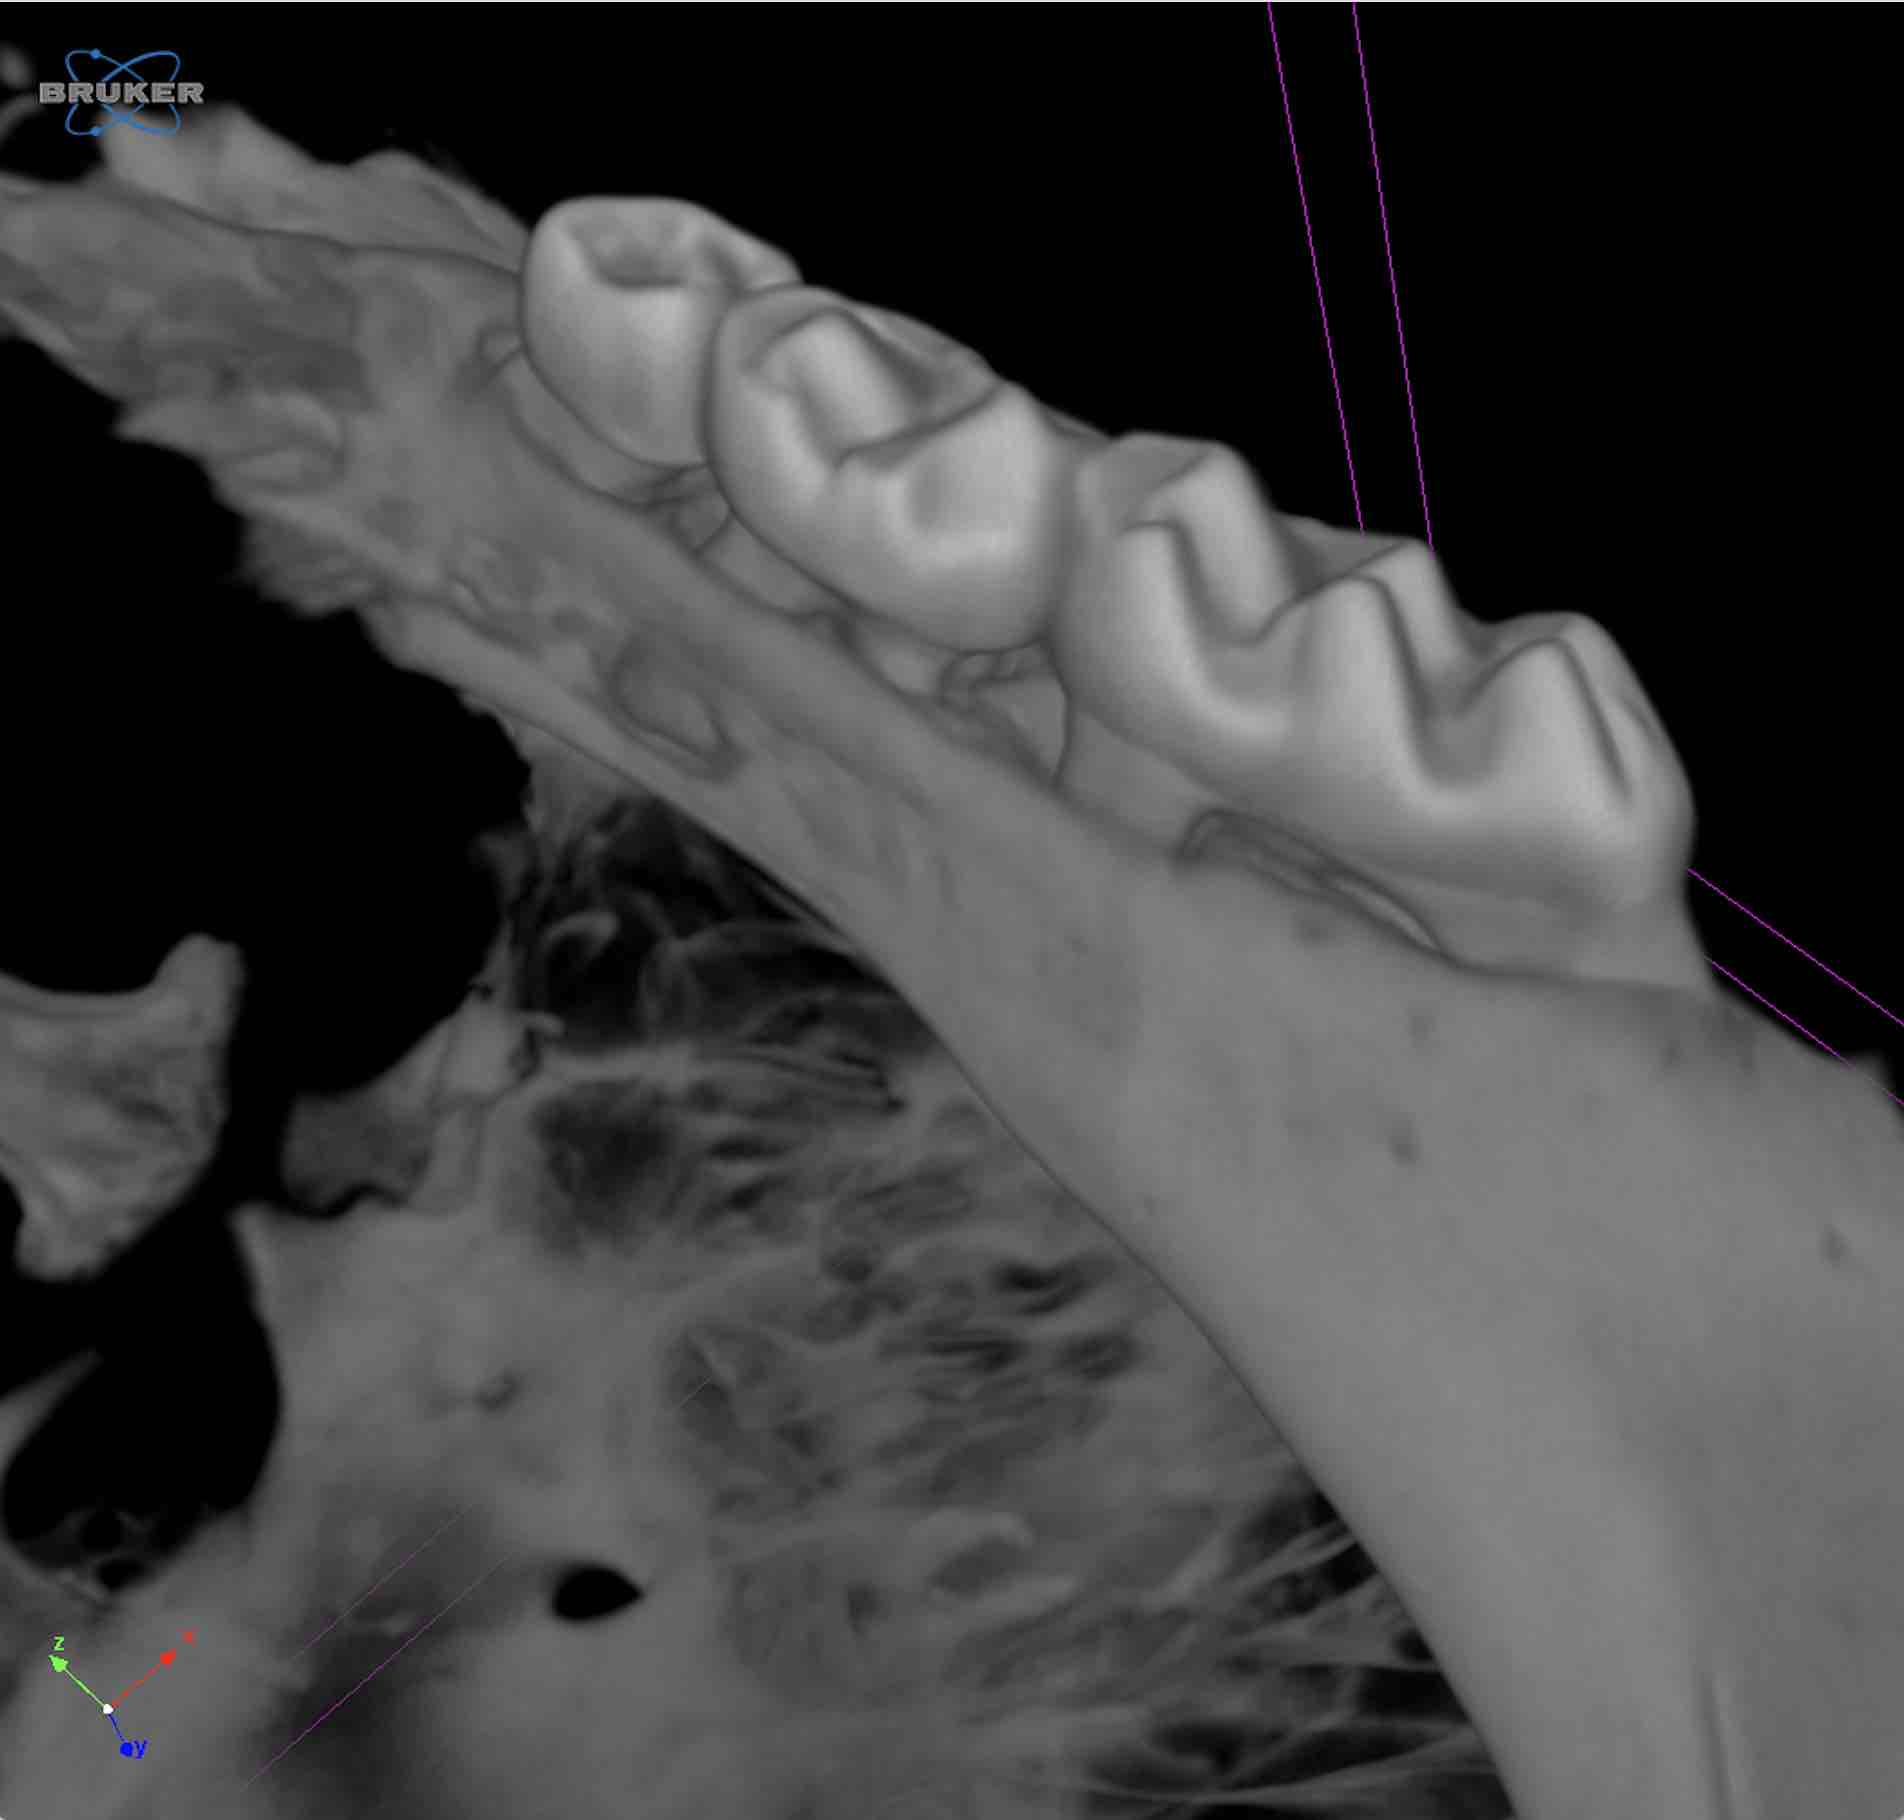

Ex vivo imaging of mouse maxilla, 3D volume rendering (Photo: Marrelli Lab)